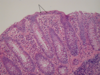

What is shown in each image?

Left: normal mucosa with villi

Right: atrophic mucosa without villi, d/t celiac disease